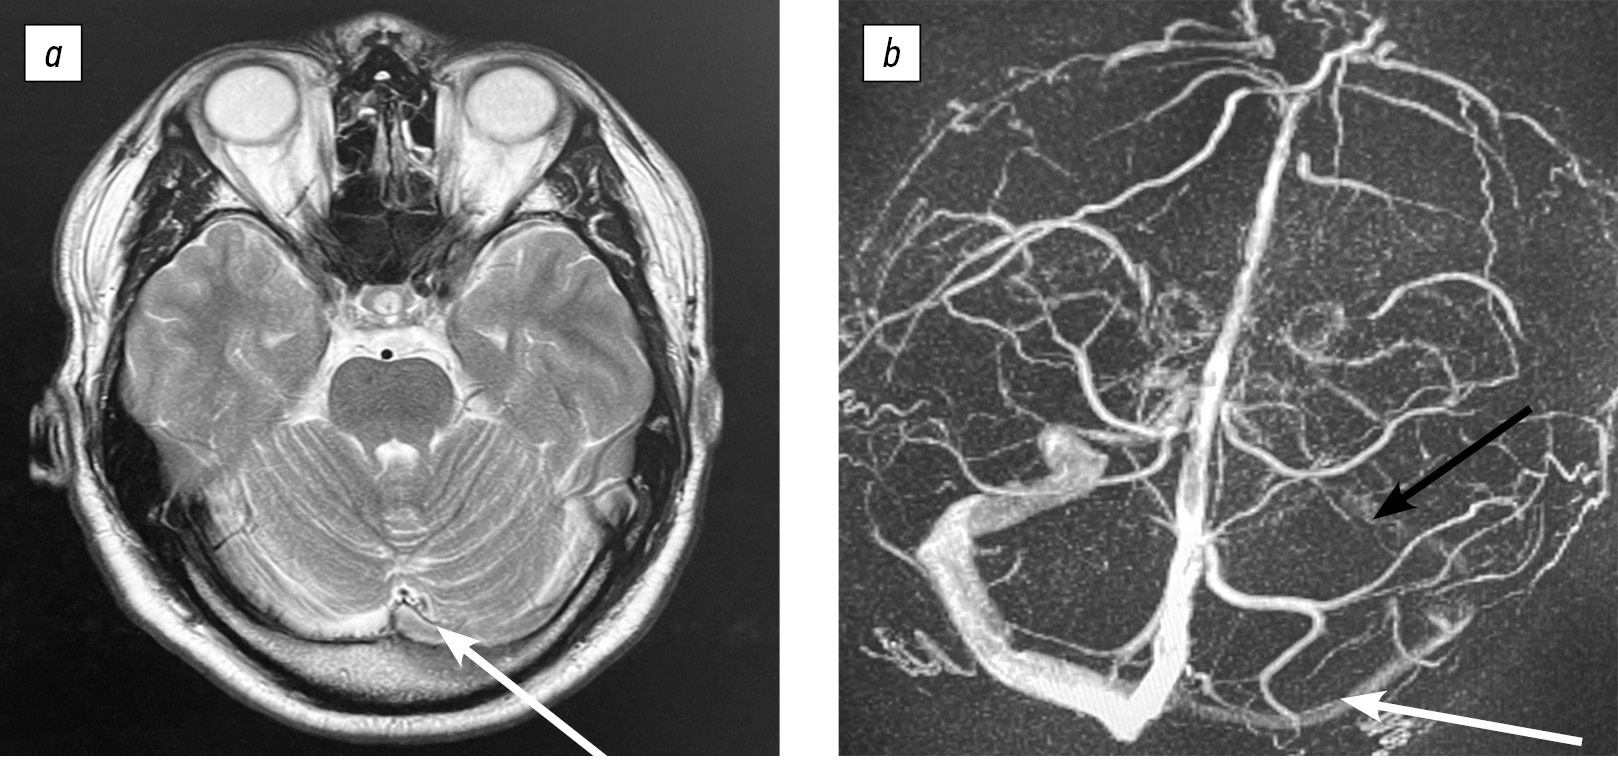

Рис. 2. Магнитно-резонансная томография головного мозга и магнитно-резонансная веносинусография до приема антикоагулянтной терапии. На нативном Т2-взвешенном изображении отмечен гиперинтенсивный сигнал от левого поперечного синуса (a). Сигнал от кровотока по тромбированному синусу диффузно снижен (b). При магнитно-резонансной веносинусографии выявлено снижение сигнала от левого сигмовидного синуса и левой яремной вены, но с сохранением кровотока (c, d).

Fig. 2. Brain magnetic resonance imaging and magnetic resonance venography prior to anticoagulant therapy initiation. On native Т2-weighted imaging, hyperintense signal from the left transverse sinus is noted (a). Blood flow signal through the thrombosed sinus appears diffusely attenuated (b). Magnetic resonance venography demonstrates signal reduction in the left sigmoid sinus and left jugular vein with preserved blood flow (c, d).

Рис. 3. Магнитно-резонансная томография головного мозга и магнитно-резонансная веносинусография через 6 мес. на фоне приема антикоагулянтной терапии. Сохранен низкий сигнал от левого сигмовидного синуса (b, черная стрелка) и частичное восстановление кровотока в левом поперечном синусе (а, b, белая стрелка).

Fig. 3. Brain magnetic resonance imaging and cerebral venous sinus magnetic resonance imaging at 6 months of anticoagulant therapy: The left sigmoid sinus maintains reduced signal intensity (b, black arrow), while the left transverse sinus shows partial blood flow recovery (a, b, white arrow).